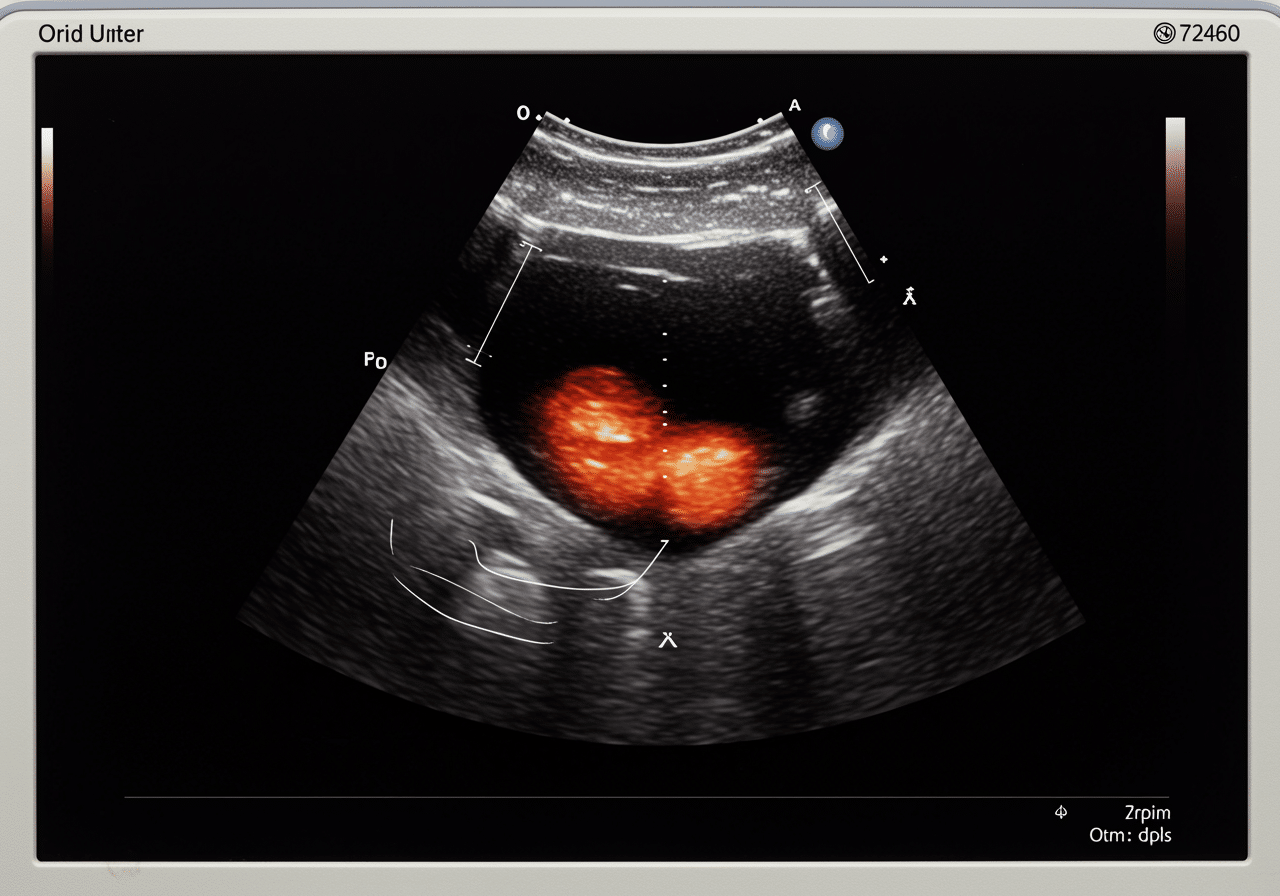

Priority ER's diagnostic capabilities for ultrasound (FAST) for internal fluid, DVT evaluation, or gallbladder inflammation exceed Joint Commission standards for emergency departments[14], featuring high-resolution portable ultrasound machines enabling immediate bedside assessment without transporting unstable patients to radiology departments. Our emergency physicians trained in emergency ultrasound perform FAST exams with 86-97% sensitivity for detecting hemoperitoneum in hypotensive patients, compression ultrasound with 95% sensitivity for proximal DVT detection, and right upper quadrant ultrasound identifying gallstones, gallbladder wall thickening, and Murphy's sign confirming acute cholecystitis with 88% sensitivity[15]. The integration of color Doppler imaging identifies absence of venous flow confirming DVT diagnosis, spectral Doppler assesses respiratory variation distinguishing acute versus chronic thrombosis, and power Doppler detects gallbladder wall hyperemia indicating acute inflammation requiring urgent surgical intervention.

Advanced imaging through our comprehensive diagnostic capabilities provides extended FAST (E-FAST) adding bilateral thoracic views detecting pneumothorax with higher sensitivity than chest x-ray, evaluation for IVC collapsibility assessing volume status guiding resuscitation, and cardiac ultrasound identifying pericardial effusion with tamponade physiology requiring emergency pericardiocentesis. For DVT evaluation, our emergency physicians perform complete lower extremity venous mapping from common femoral vein through posterior tibial and peroneal veins when clinical suspicion remains high despite negative compression ultrasound in proximal veins. This comprehensive approach explains why the American College of Emergency Physicians supports emergency physician-performed point-of-care ultrasound as standard practice, improving diagnostic accuracy from 75% (clinical examination alone) to 96% (examination plus bedside ultrasound).

Compression ultrasound detects proximal DVT (common femoral and popliteal veins) with 95% sensitivity and 96% specificity, making it the gold standard for DVT diagnosis. Priority ER emergency physicians perform two-point compression (common femoral and popliteal) or complete examination including calf veins based on clinical probability. Inability to completely compress vein indicates thrombus presence requiring immediate anticoagulation. Color Doppler confirms absent flow, while spectral Doppler assesses respiratory variation helping differentiate acute versus chronic thrombosis. Negative ultrasound with high clinical suspicion (Wells score ≥2) may require D-dimer testing or repeat ultrasound in 5-7 days.